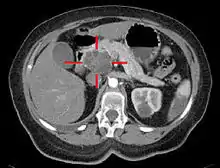

![]() Мікрофотознімок аденокарциноми підшлунковoї залози (фарбування гематоксиліном-еозином) Мікрофотознімок аденокарциноми підшлунковoї залози (фарбування гематоксиліном-еозином) | |

При підозрі на РПЗ пацієнтам рекомендовано проведення КТ (з контрастуванням) та УЗД органів черевної порожнини — обидва високо-інформативні інструментальні неінвазивні методи дослідження. Для діагностики РПЗ рутинно визначають концентрацію в крові специфічного до РПЗ маркеру СА19-9 та CEA, що є більш загальним індикатором неопластичного процесу.